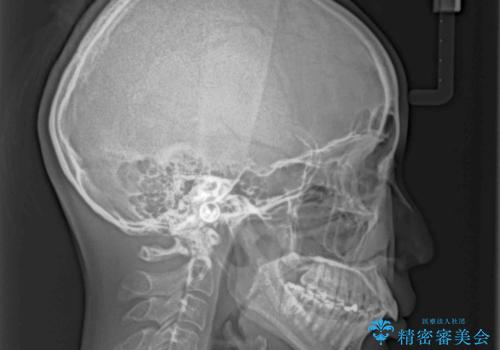

- 飛び出した前歯を気にして来院された患者様です。

口元を引っ込めるために上下左右の第一小臼歯4本を抜歯することとしました。

結婚式を行う予定があるとのことで、表側のワイヤー装置で、速やかに治療を終えられるようにしました。